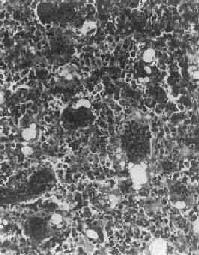

镜下观,肿瘤的分化程度差异很大,分化好的软骨肉瘤在镜下易误诊为软骨瘤,但在肿瘤的边缘可以找到瘤细胞的异型性,如核肥大、深染,出现较多的双核、巨核和多核瘤巨细胞,并可见明显核仁(图17-4)。在分化差的软骨肉瘤则上述瘤细胞的异型性很明显,核分裂像也多见。软骨肉瘤的基质可为与一般透明软骨相似的透明基质,也可为粘液样基质,常见于恶性程度高的软骨肉瘤。

图17-4 软骨肉瘤

软骨细胞大小不等,有的较大。许多细胞有肥硕的胞核,有的有双核